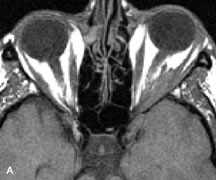

Cavernous hemangiomas appear as well-circumscribed, smooth, usually intraconal masses that are isointense to muscle on T1-weighted images and hyperintense on T2-weighted images (Fig. 12). Patchy early enhancement is typically followed by diffuse, more homogeneous enhancement.39 The internal architecture of the mass, including septation and internal vasculature, may often be appreciated with high-quality orbital imaging.40

Fig. 12. A. T1- and (B) T2-weighted MR scans demonstrate a well-circumscribed intraconal mass causing severe optic nerve displacement. These lesions are usually intermediate in signal intensity on T1-weighted scans and very hyperintense on T2-weighted Images. C and D. Postcontrast fat-suppressed T1-weighted scans demonstrate characteristic patchy intense enhancement that becomes more complete from the initial postcontrast scan (C) to a more delayed scan (D).